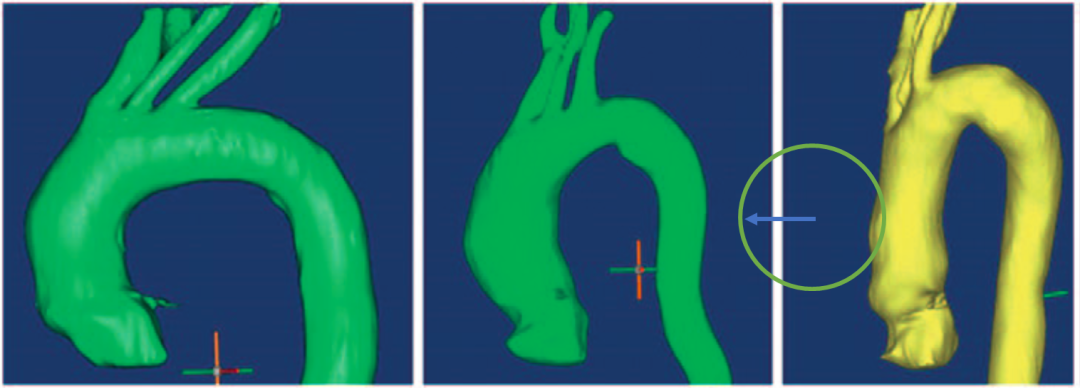

3D主动脉影像

主动脉3D打印模型